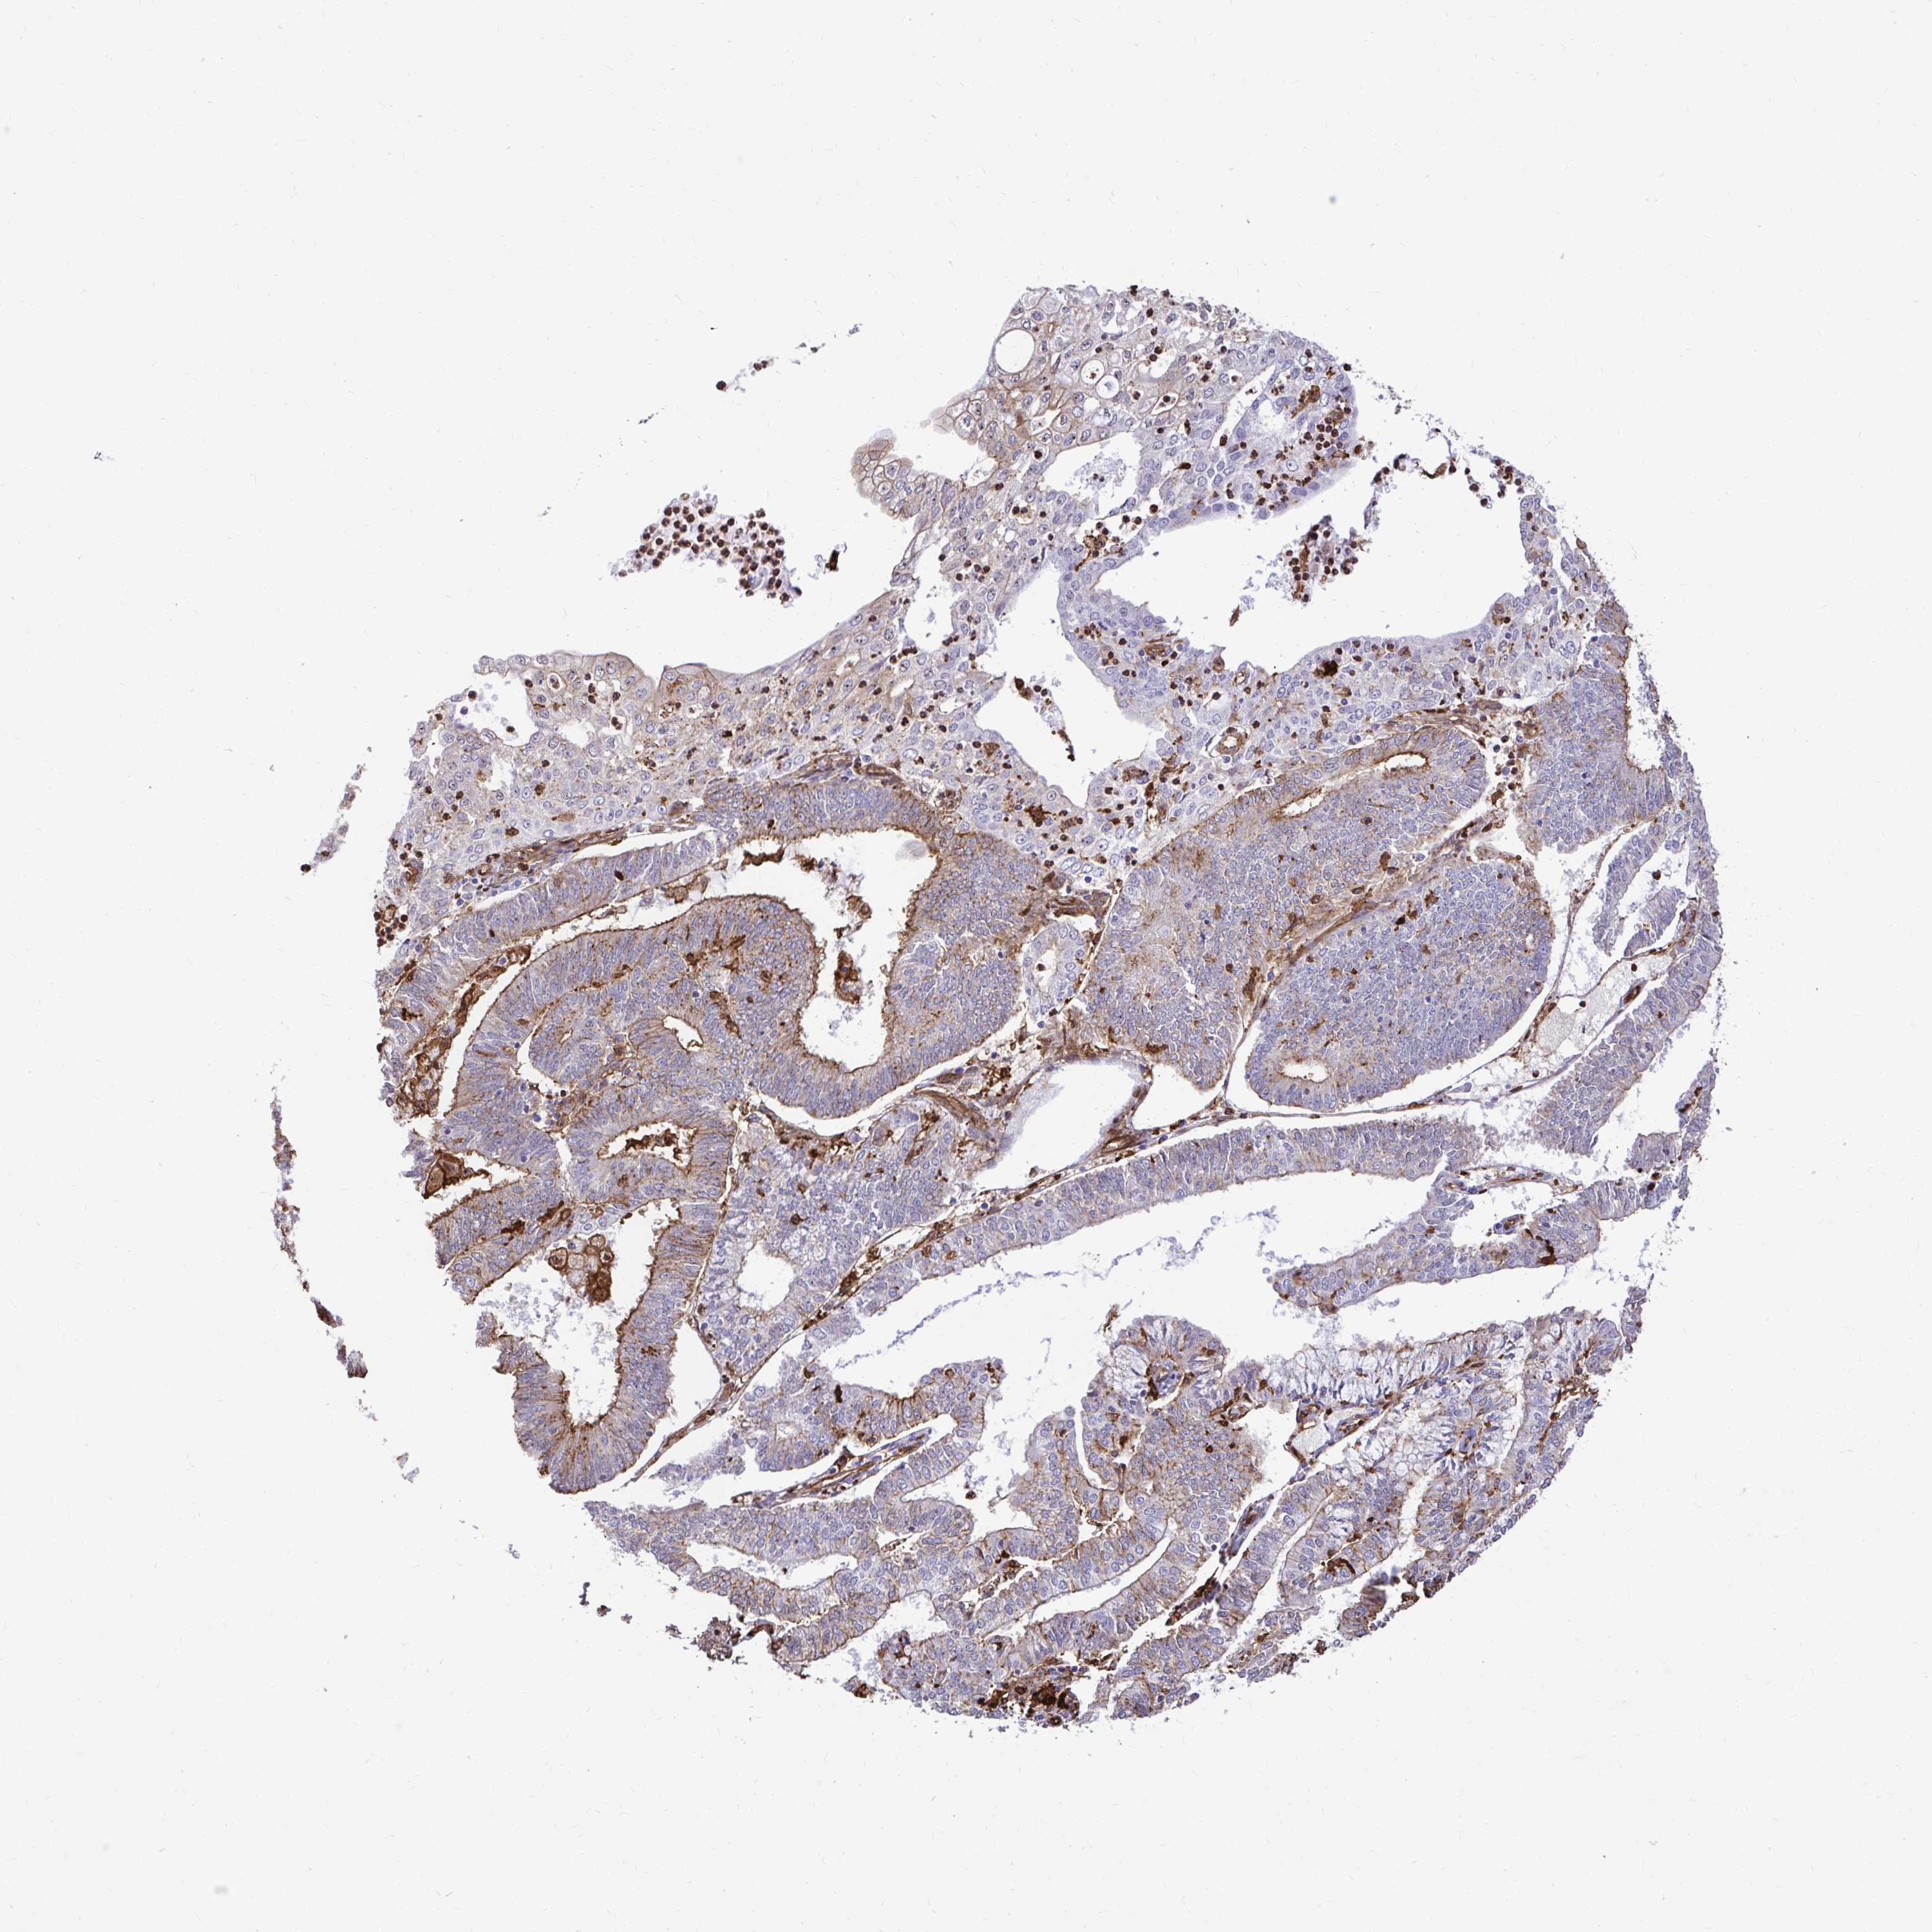

ENDOMETRIAL CANCER - Protein expressioni

A mouse-over function shows sample information and annotation data. Click on an image to view it in a full screen mode. Samples can be filtered based on level of antibody staining by selecting one or several of the following categories: high, medium, low and not detected. The assay and annotation is described here.

Note that samples used for immunohistochemistry by the Human Protein Atlas do not correspond to samples in the TCGA dataset.

Antibody stainingi

Antibody staining in the annotated cell types in the current human tissue is reported as not detected, low, medium, or high, based on conventional immunohistochemistry profiling in selected tissues. This score is based on the combination of the staining intensity and fraction of stained cells.

Each image is clickable and will lead to virtual microscopy that enables deeper exploration of all samples and also displays staining intensity scores, fraction scores and subcellular localization as well as patient and tissue information for each sample.

Antibody HPA054026

Antibody CAB010823

Antibody CAB016728

Antibody CAB036009

Staining

High

Medium

Low

Not detected

Intensity

Strong

Moderate

Weak

Negative

Quantity

>75%

75%-25%

<25%

None

Location

Nuclear

Cytoplasmic/membranous

Cytoplasmic/membranous,nuclear

Adenocarcinoma, NOS

Adenocarcinoma, metastatic, NOS